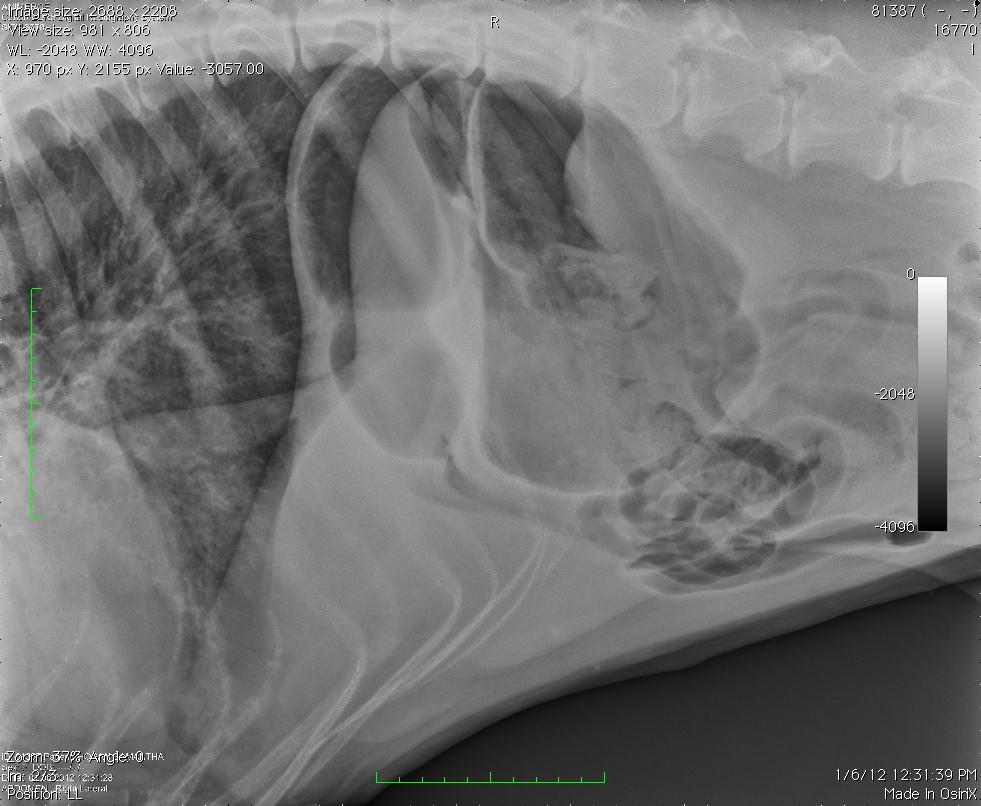

An 8-year-old FS Great Dane dog with a history of urinary tract infection and VPCs was presented for evaluation of lethargy and weakness in the hind limbs. Elevated ALP activity and BUN was present on serum biochemistry.

An 8-year-old FS Great Dane dog with a history of urinary tract infection and VPCs was presented for evaluation of lethargy and weakness in the hind limbs. Elevated ALP activity and BUN was present on serum biochemistry.